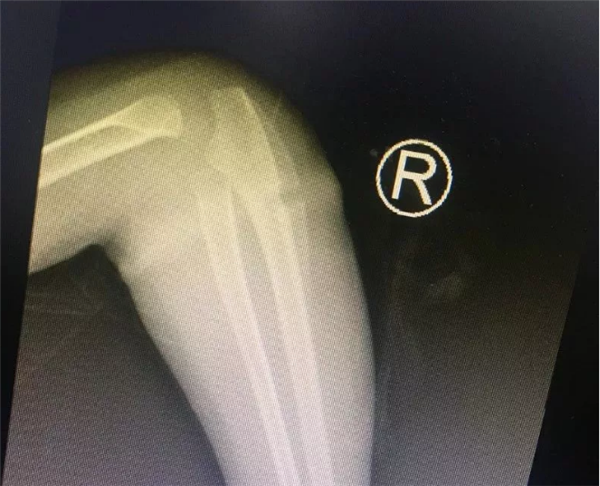

4岁的乐乐长期跟着爷爷奶奶生活,不知从什么时候开始,右侧手臂莫名其妙长了一圈“圆环”。最初家里人没有在意这个“圆环”,哪知道乐乐的右前臂一天比一天更红肿。2018年过年后,乐乐手臂严重肿胀,疼痛,而且手指活动受限。看到孩子右前臂比左前臂足足肿大了一圈,这时乐乐的家人才担心起来。

叶主任看了乐乐的手臂,告诉孩子的家长,“圆环”很可能是橡皮筋导致的。虽然乐乐父母不大相信,还是听从叶主任的建议,让乐乐入院了。没多久,入院后B超检查结果出来了,也证实了叶主任的诊断是正确的。

有了明确的诊断,骨科各位医生开始为乐乐手术。这个手术并不难,无影灯下,历经半小时就将“圆环”擒拿归案,把长在肉里的环形橡皮筋取了出来,彻底解决了乐乐的病痛。